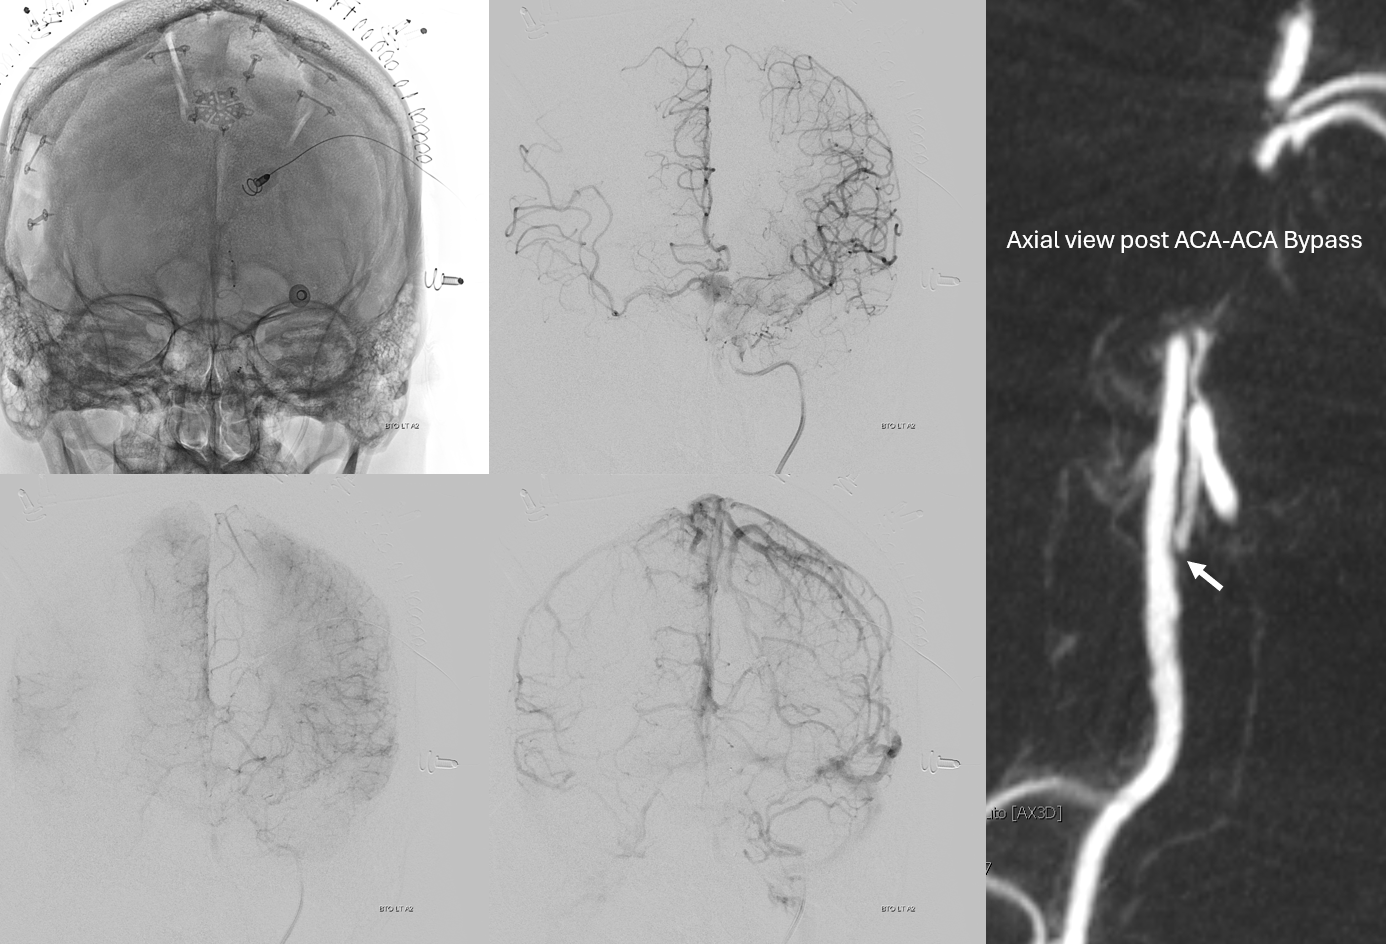

Bypass working even better

PCOM working correspondingly less. Ophthalmic no longer needed

Bilateral CBCT Injections. A big bonus — the ACA-ACA bypass now seems to be patent! Cant see that from 2D images really at this stage. We did not realise this at first but became clear later

A3-A3 bypass more images

Stereo views of the two craniotomies, with translucent and sonolucent closure